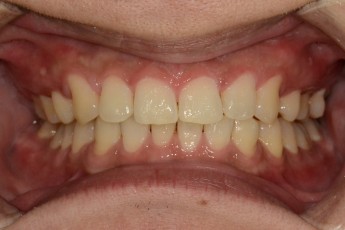

Before

After